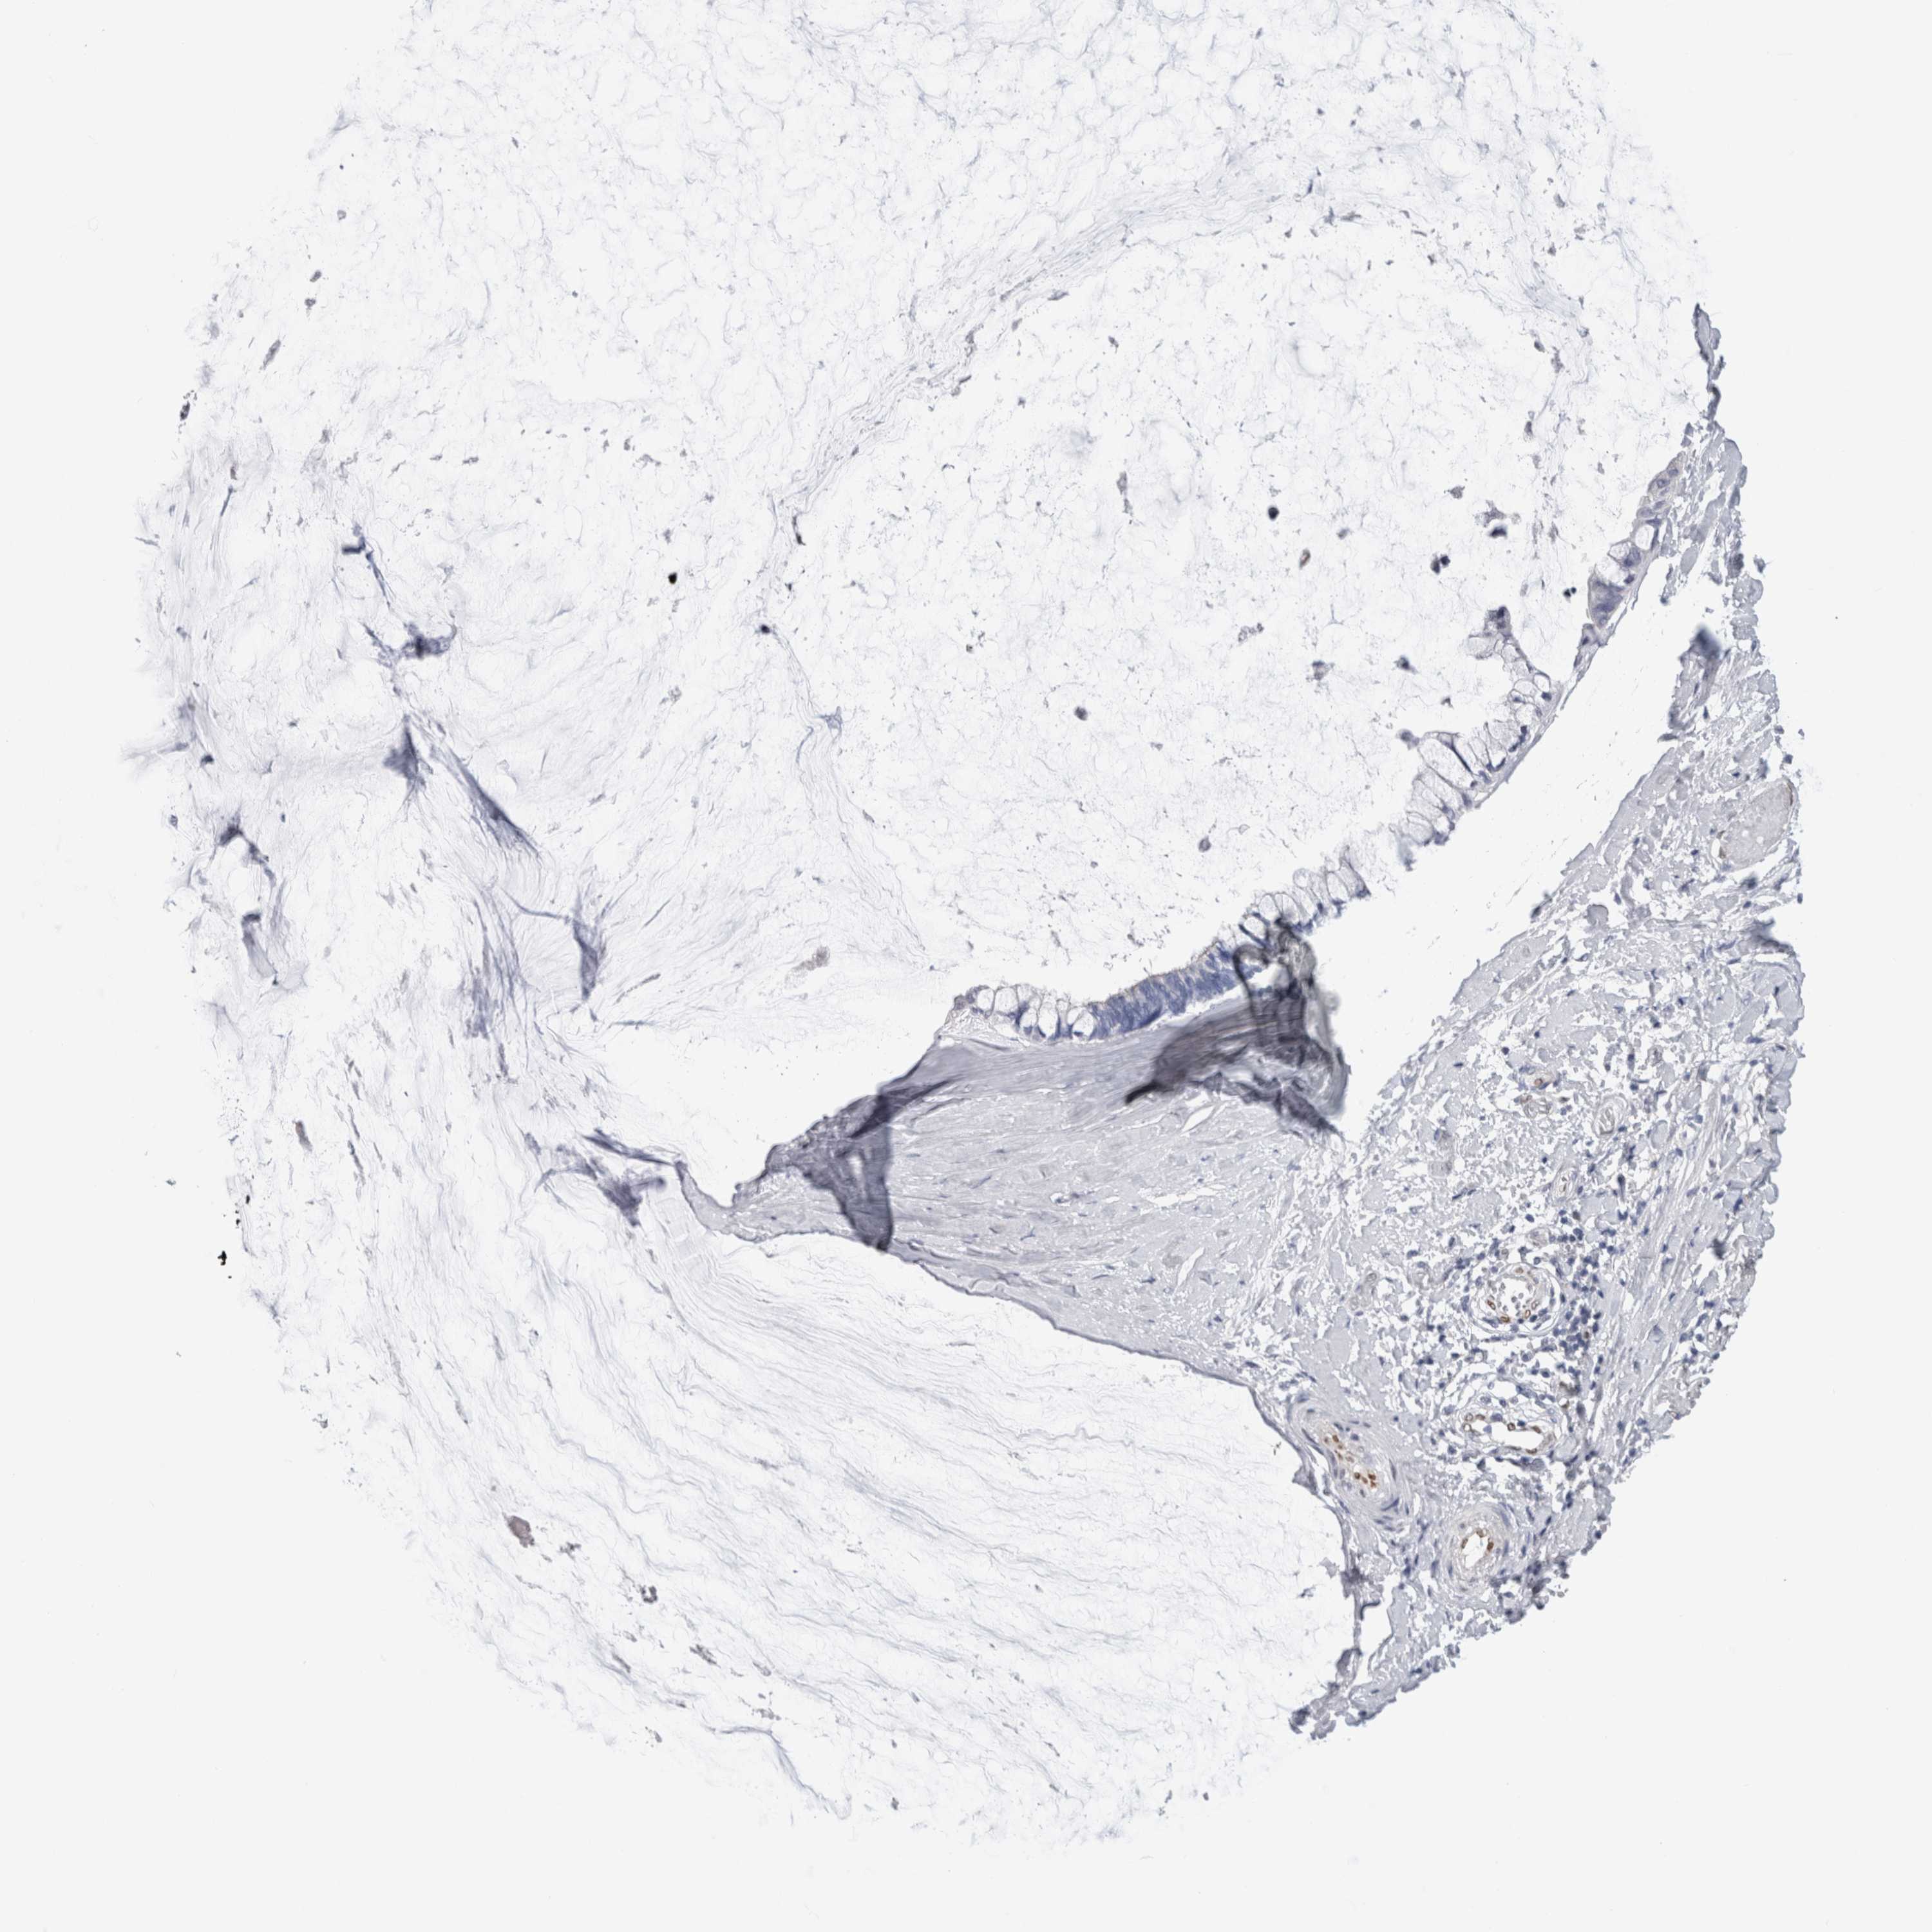

OVARIAN CANCER - Protein expressioni

A mouse-over function shows sample information and annotation data. Click on an image to view it in a full screen mode. Samples can be filtered based on level of antibody staining by selecting one or several of the following categories: high, medium, low and not detected. The assay and annotation is described here.

Note that samples used for immunohistochemistry by the Human Protein Atlas do not correspond to samples in the TCGA dataset.

Antibody stainingi

Antibody staining in the annotated cell types in the current human tissue is reported as not detected, low, medium, or high, based on conventional immunohistochemistry profiling in selected tissues. This score is based on the combination of the staining intensity and fraction of stained cells.

Each image is clickable and will lead to virtual microscopy that enables deeper exploration of all samples and also displays staining intensity scores, fraction scores and subcellular localization as well as patient and tissue information for each sample.

Antibody HPA024426

Antibody CAB007057

Cystadenocarcinoma, serous, NOS

Carcinoma, endometroid

Cystadenocarcinoma, mucinous, NOS

Carcinoma, NOS